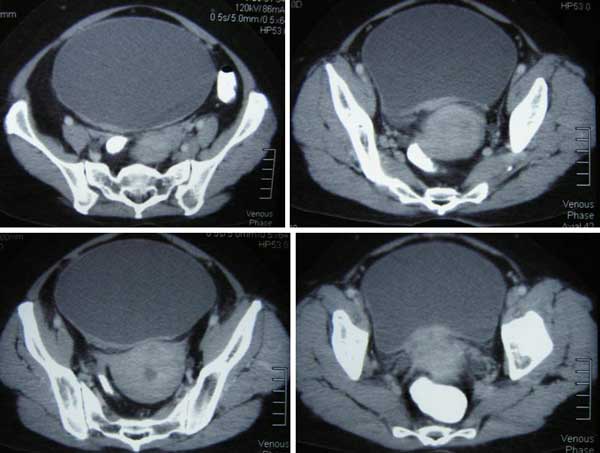

Pasien adalah seorang warnita berusia 56 tahun dari Medan, Indonesia. Pada Maret-April 2012, dia sakit perut diikuti dengan pendarahan. Dia mual dengan perutnya kembung. Dokter di Medan mendiagnosanya sebagai kanker serviks (leher rahim). Pasien datang ke rumah sakit swasta di Penang karena dia tidak bisa buang air kecil. Dia diberi tahu ini disebabkan karena pembengkakan ginjal nya. Sebuah kateter dipasang. Dia kemudian dirujuk ke dokter kandungan yang mengatakan bahwa kankernya telah menyebar ke kandung kemihnya.

Biopsi dilakukan. Laporan histopathologi mengatakan non keratinising squamous sel karsinoma. Pasien kemudian dirujuk ke onkolog. Dokter Onkologi menyarankan radioterapi. Pasien dan keluarganya menolak pengobatan dan kembali ke Medan. Pasien disuruh kembali ke Penang lagi setelah tiga bulan. Namun, setelah sebulan dan seminggu di rumah, pasien tidak bisa buang air kecil lagi. Masalah itu diselesaikan setelah kateter yang dipasang sebelumnya diganti. Namun demikian, pasien mengalami nyeri, mual dan muntah. Dia tidak bisa buah air besar selama lima hari terakhir dan kemudian buang air kecil nya diblokir lagi. Dokter harus ganti kateter untuk menyelesaikan masalahnya.